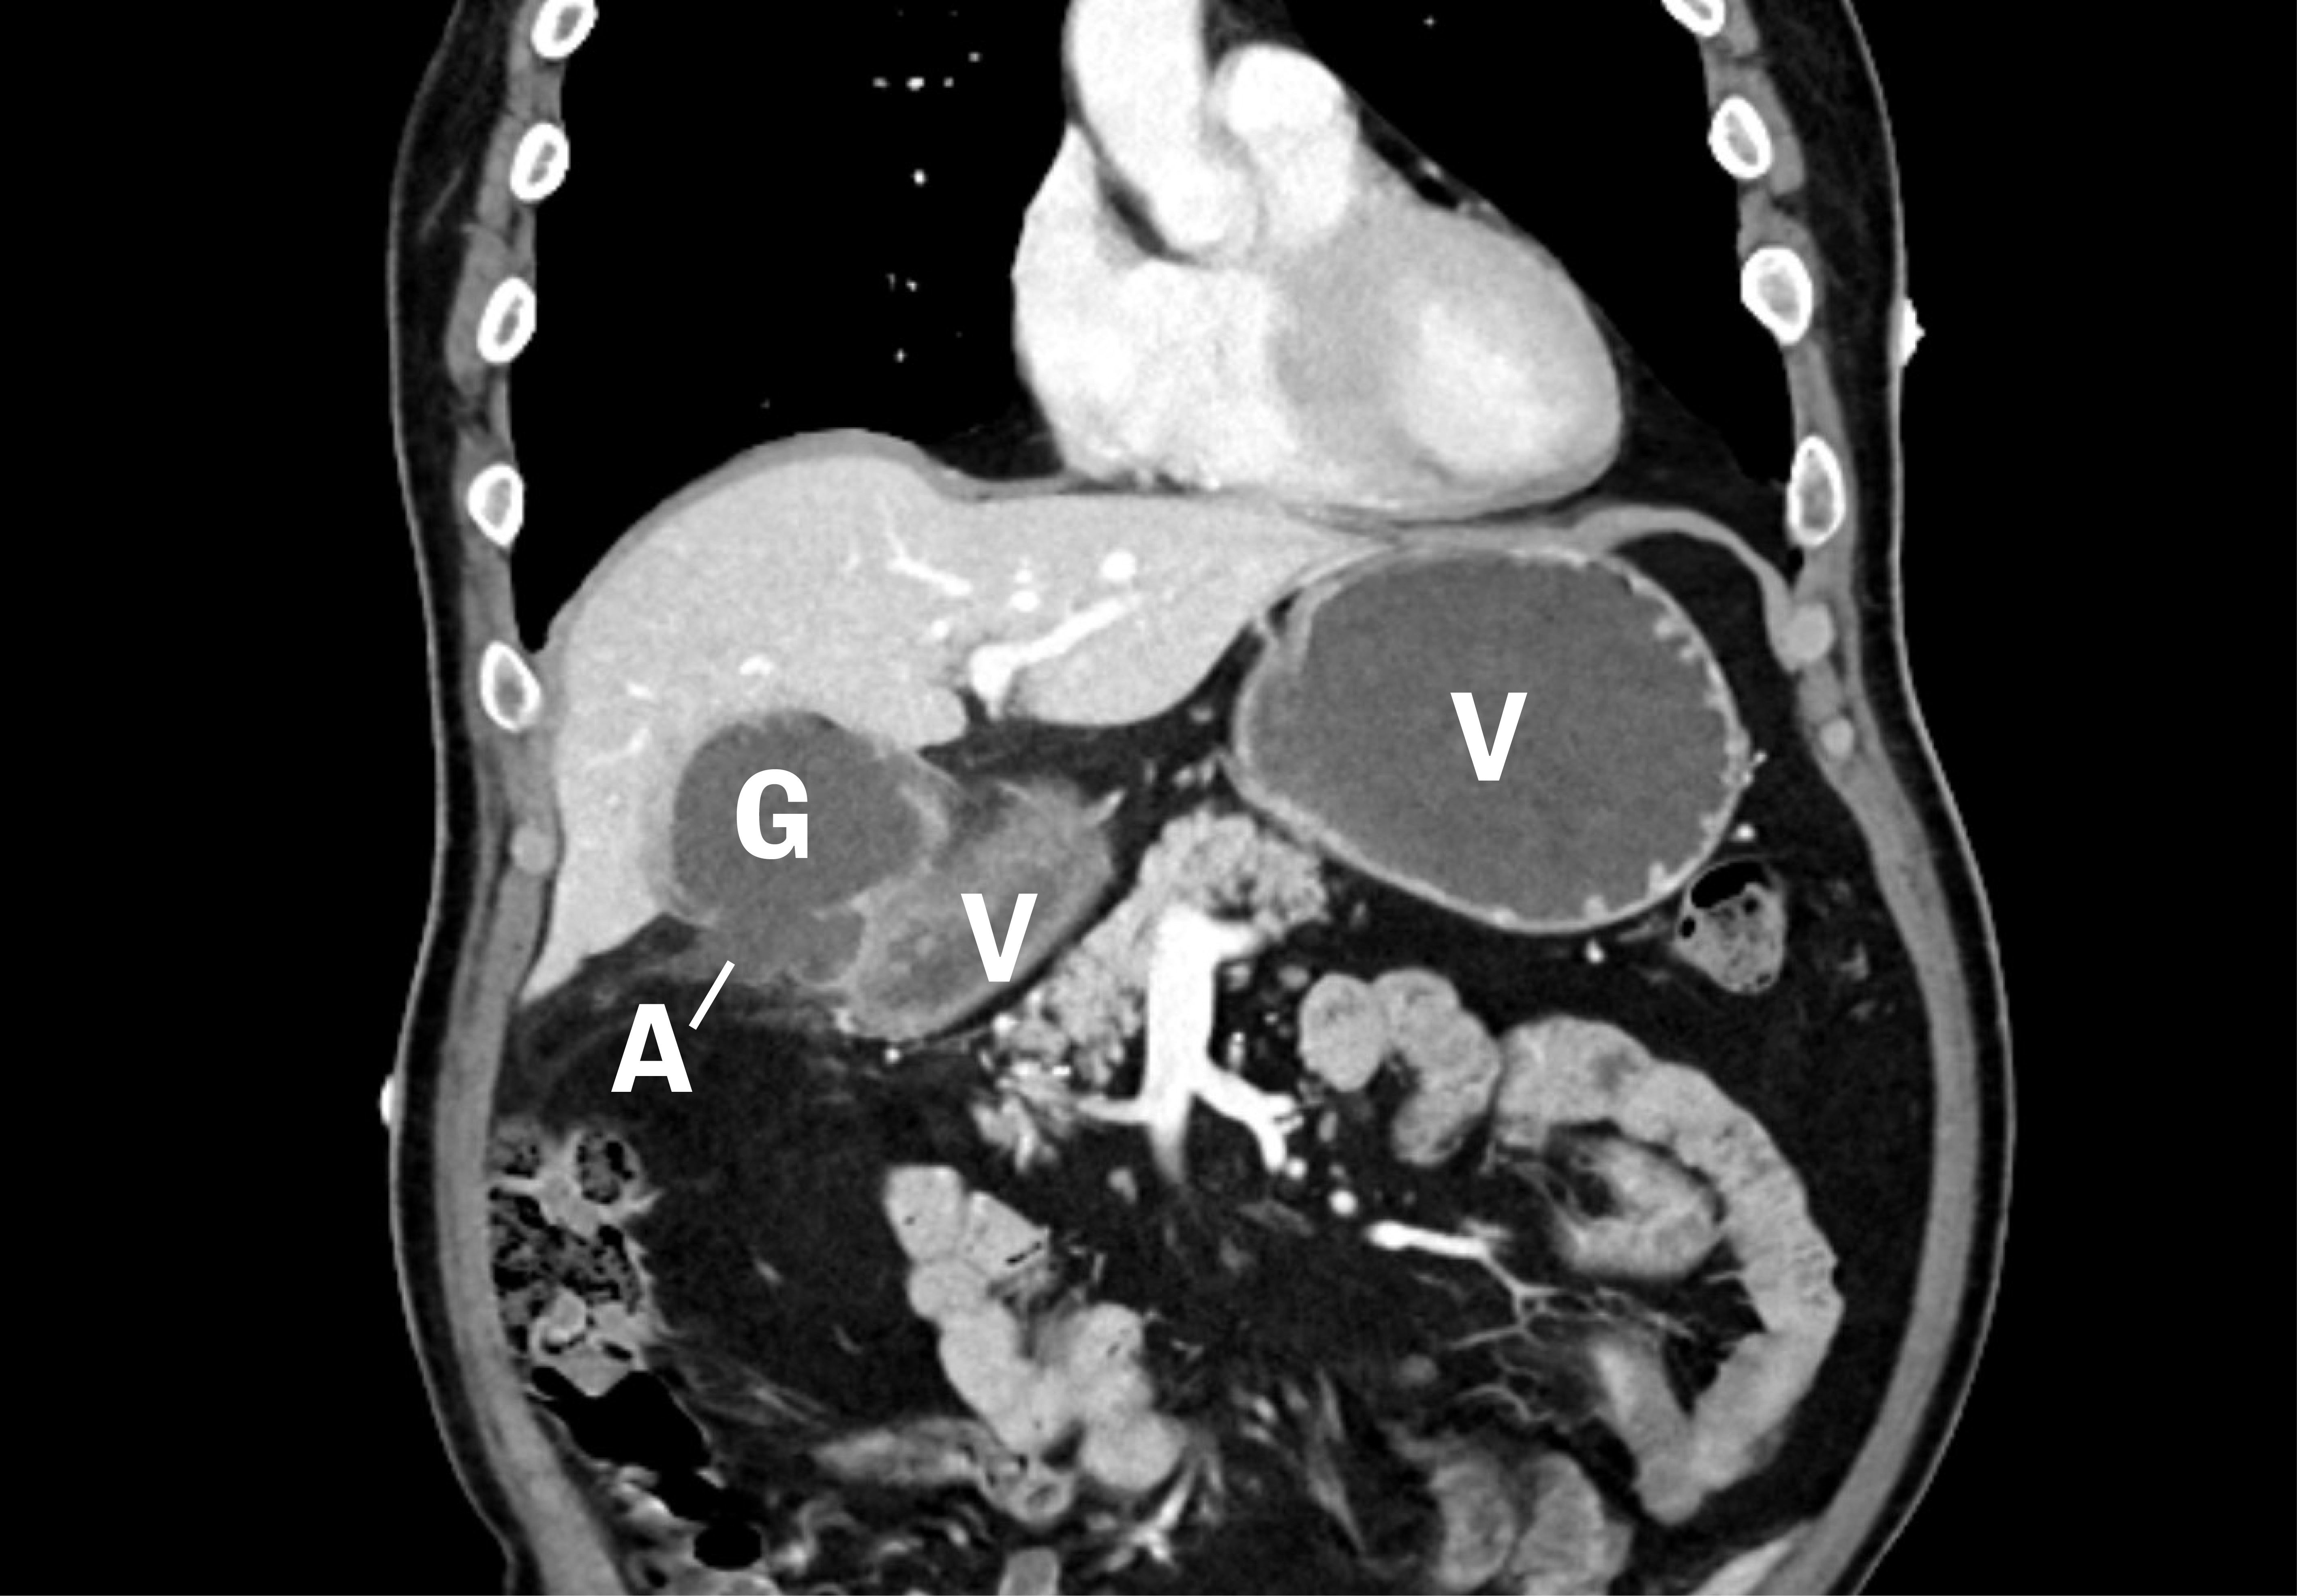

Dag 2 hadde pasienten lett fallende leukocytter 13,9 · 109/L (3,5–10), CRP 41 mg/L (< 4), ALP 120 U/L (35–105) og pankreasamylase 69 U/L (10–65), ellers var tilstanden uendret. Vi vurderte intraabdominal abscess, pankreatitt eller malignitet som aktuelle differensialdiagnoser, og henviste derfor til CT-undersøkelse av toraks og abdomen som viste en veggfortykket galleblære med økt kontrastoppladning, samt en defekt i galleblæreveggen medialt med en væskeansamling på 6,2 × 4,6 cm nær galleblæren og ventrikkel antrum. I tillegg fantes moderate reaktive forandringer i fettvevet rundt, samt noe markert ventrikkelvegg og nærliggende diafragma. Dette ble tolket som en kolecystitt med perforasjon, hvor det var dannet et avkapslet lokulament mellom galleblære og ventrikkel. Dette lokulamentet kommuniserte med galleblæren (figur 1).